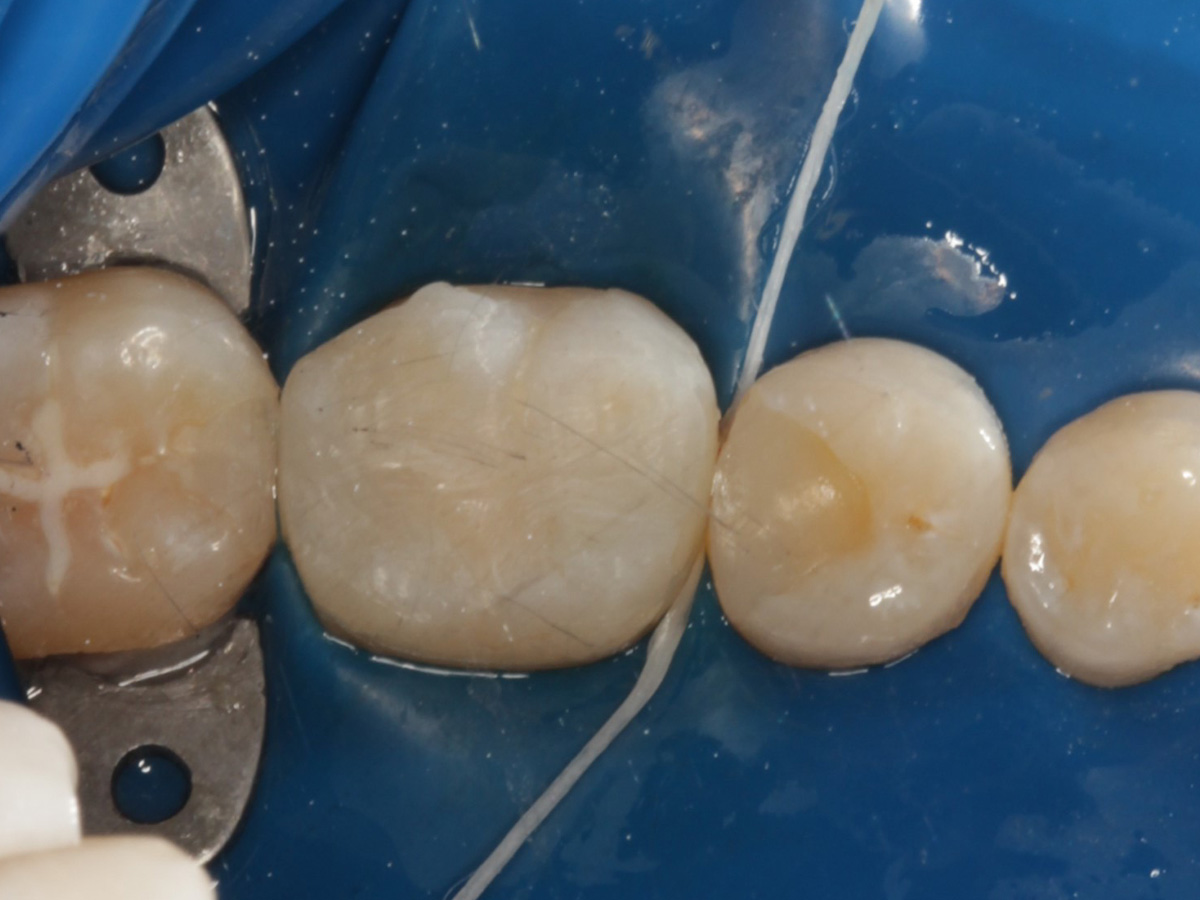

Abbildung 12

Applikation der Matrizen: Evolve Blau Molar 5 mm distal und 6 mm mesial